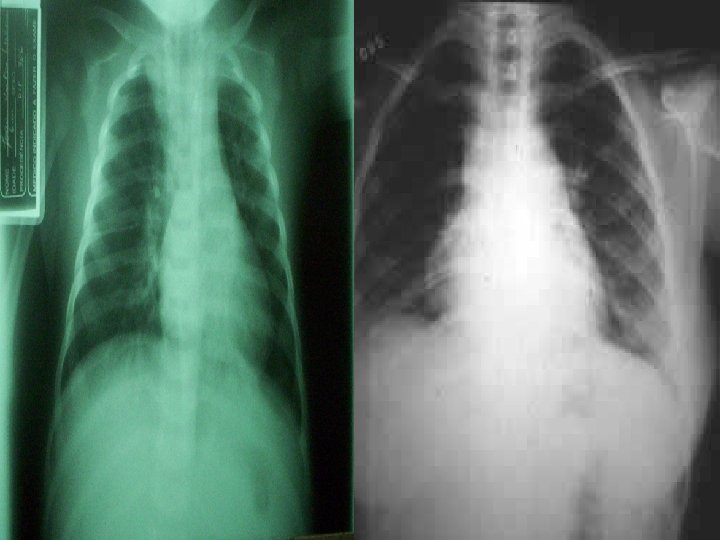

MANIFESTAÇÕES CLÍNICAS n n Achados da radiografia: infiltrados intersticiais ou doença alveolar difusa que progride rapidamente. Às vezes surgem lesões nodulares, infiltrados raiados ou lobares, derrames pleurais. Diagnóstico: Demonstração do P. carinii por coloração apropriada com prata de lavado broncoalveolar; raramente a biópsia é necessária.

MANIFESTAÇÕES CLÍNICAS n n PNEUMONIA VIRAL Vírus Sincicial respiratório (RSV), parainfluenza e adenovírus Manifestações: Rinite e tosse, febre em temperaturas mais baixas que nas PNM bacterianas, taquipnéia com tiragem e batimento de asas do nariz, cianose e fadiga respiratória. Ausculta: Estertores e sibilos difusos, indistinguível da doença por micoplasma.

MANIFESTAÇÕES CLÍNICAS n n n Diagnóstico: RX de tórax com infiltrados difusos, hiperinsuflação. Contagem de leucócitos normal ou levemente elevada (<20000), com linfócitos predominantes. Reagentes de fase aguda normais ou levemente aumentados. Diagnóstico definitivo: Isolamento do vírus em amostra do trato respiratório e sorologias.

MANIFESTAÇÕES CLÍNICAS n n n Contagem de leucócitos elevada, com predomínio de polimorfonucleares. Gasometrias arteriais mostram hipoxemia, sem hipercapnia. Achados Radiográficos: consolidações, infiltrado e derrame em alguns casos. Tratamento: Penicilina G, se S. pneumoniae resistente, cefalosporinas de terceira geração. Caso haja resistência com estes últimas, vancomicina (CULTURA)

MANIFESTAÇÕES CLÍNICAS n n n Manifestações e laboratório similares ao das outras PNM bacterianas. RX: grandes derrames pleurais e pneumatoceles. Elevação da ASLO. Swab de orofaringe, secreções nasofaríngeas ou escarro. Tratamento: Penicilina G

MANIFESTAÇÕES CLÍNICAS n n PNEUMONIA ESTAFILOCÓCICA Causam broncopneumonia confluente, muitas vezes unilateral, ou mais proeminente em um dos lados (RX compatível). Numerosos abcessos, podendo ocorrer piopneumotórax.